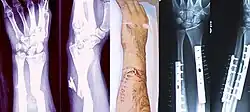

- Forearm fracture

- Radius fracture

- Distal radius fracture

- Hand fracture